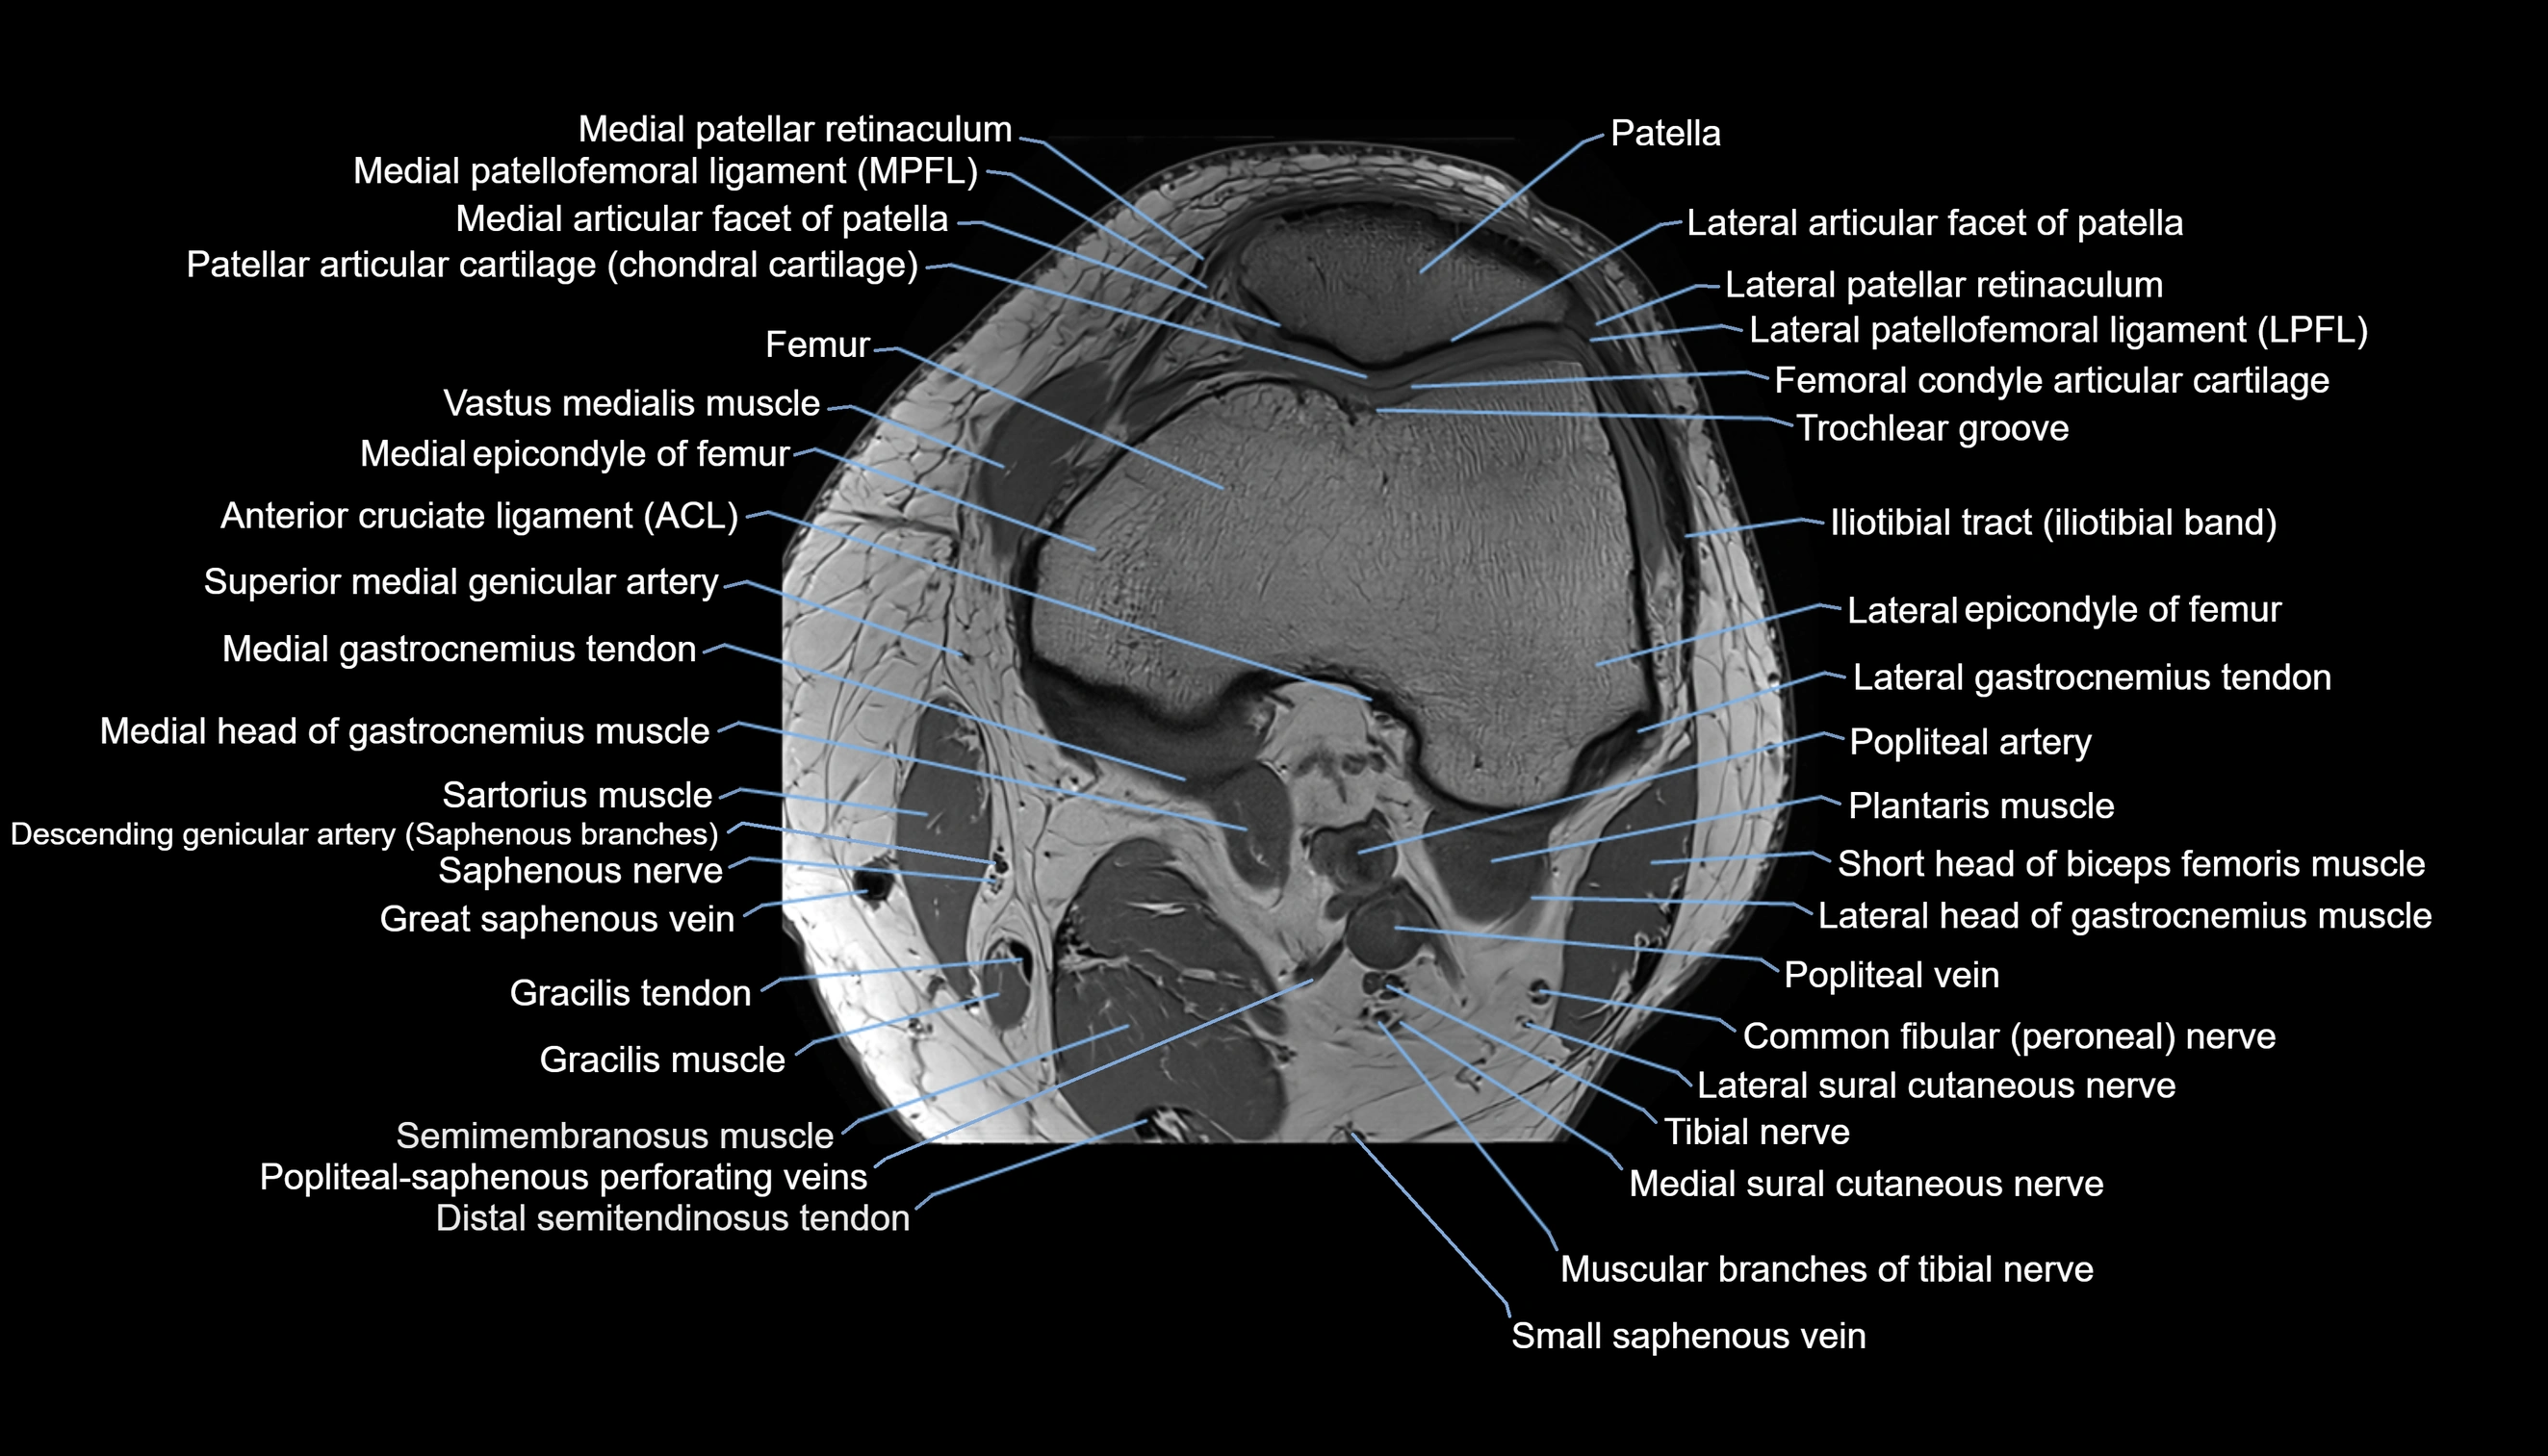

- Knee Joint

- Lateral articular facet of patella

- Lateral border of patella

- Lateral patellar retinaculum

- Lateral patellofemoral ligament

- Medial articular facet of patella

- Medial border of patella

- Medial epicondyle of femur

- Medial gastrocnemius tendon

- Medial head of gastrocnemius muscle

- Medial patellar retinaculum

- Medial patellofemoral ligament

- Medial sural cutaneous nerve

- Muscular branches of tibial nerve

- Patella

- Patellar articular cartilage

- Popliteal artery

- Popliteal vein

- Saphenous nerve

- Sartorius muscle

- Semimembranosus muscle

- Small saphenous vein

- Superior medial genicular artery

- Tibial nerve

- Trochlear groove

- Vastus medialis muscle